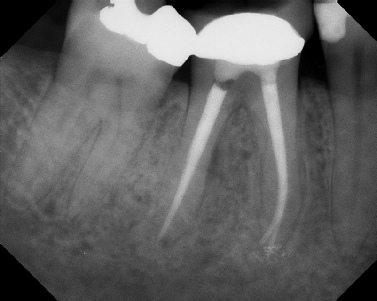

COMPLICATED ANATOMY LARGE LESIONS CALCIFIED CANALS PERFORATION / RESORPTION SEPARATED INSTRUMENTS SURGICAL CASES RETREATMENT / pOST REMOVAL OPEN APICES ACCESS THRU CROWNS Root Canal Case Portfolio

Pre-op Post-op 6 mos.